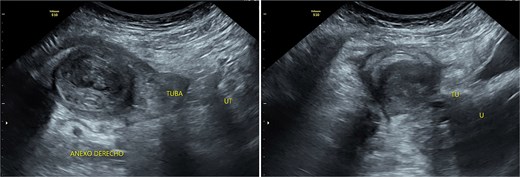

Stage III pelvic inflammatory disease (PID) was suspected based on ultrasound (Figs 1–3) and gynecological examination, which revealed mild bulging of the right lateral fornix, cervical motion tenderness, and a white, non-foul-smelling vaginal discharge. Empiric intravenous antibiotic therapy was initiated, followed by exploratory laparotomy via a Pfannenstiel incision. Intraoperative findings included an 8 × 5 cm uterus, edematous fallopian tubes, and a simple 5 × 5 cm left adnexal cyst. Cystectomy was performed.

Transpelvic ultrasound reveals a heterogeneous mass adjacent to the right adnexa measuring 4.6 × 8.4 cm, predominantly hypoechoic with anechoic areas.